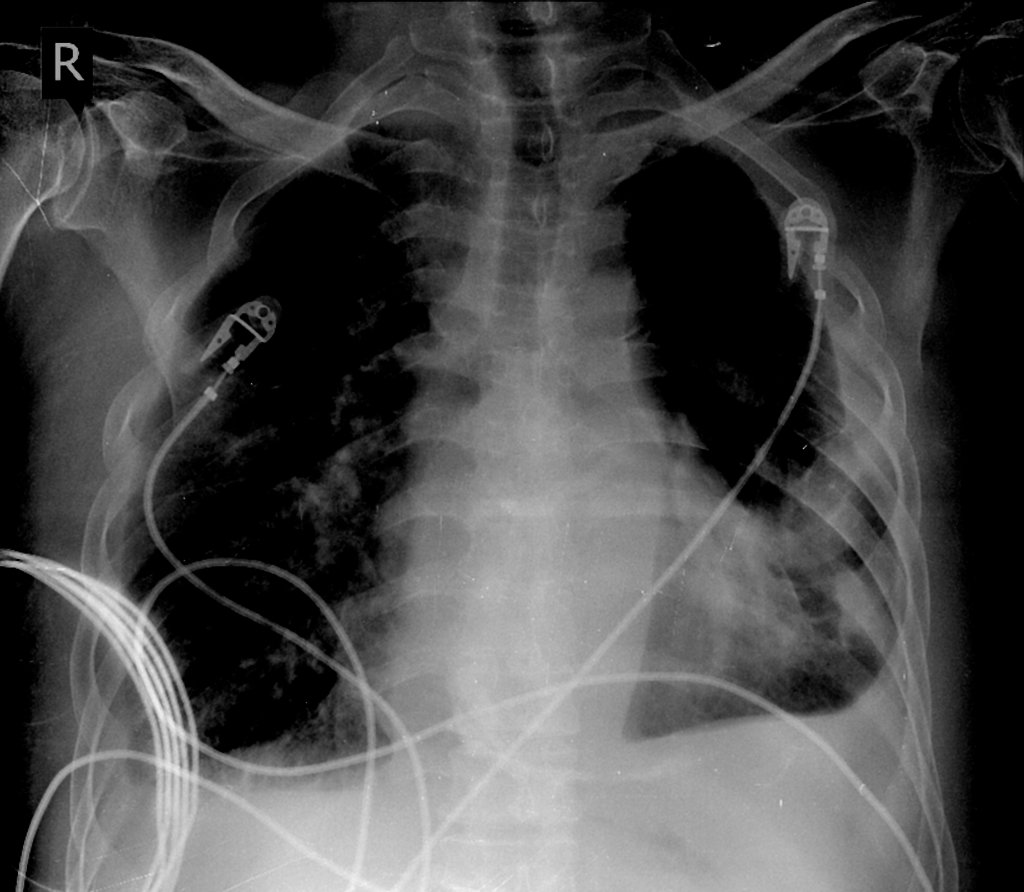

Salut les amis 🎉 Marre des ECG ? On passe à l'imagerie ! Homme, 71 ans, post-op de remplacement valvulaire. Qu'en pensez-vous ? 🌐 Interprétation : https://t.co/g0roNBNZBT #Radiologie #RadiographieThoracique #EDN